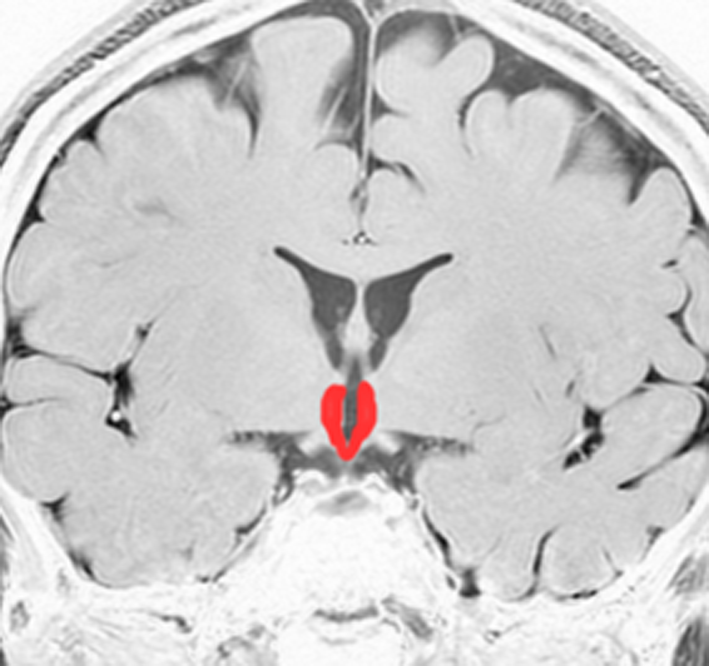

視床下部と下垂体を横から見たところ

- 視床下部と下垂体の大まかな拡大図です。視床下部から視床下部ホルモンと神経伝達が出て,下垂体茎(下垂体柄とも言います)を伝わって,下垂体の前葉と後葉からホルモンが血液の中に出て体中に広がります。

- 視床下部には食欲の中枢とか,睡眠の中枢とか,体の中の水分や塩分の調節をする中枢とか,体内時計とか,いろいろ複雑でな高度な働きがあります。

- 下垂体の前葉からは,成長ホルモン GH,プロラクチン PRL,甲状腺刺激ホルモン TSH,副腎皮質刺激ホルモン ACTH,性腺刺激ホルモン LH & FSHなどが出ます。

- 下垂体の後葉からは,おしっこの量を調節する抗利尿ホルモン ADHというのが出ます。